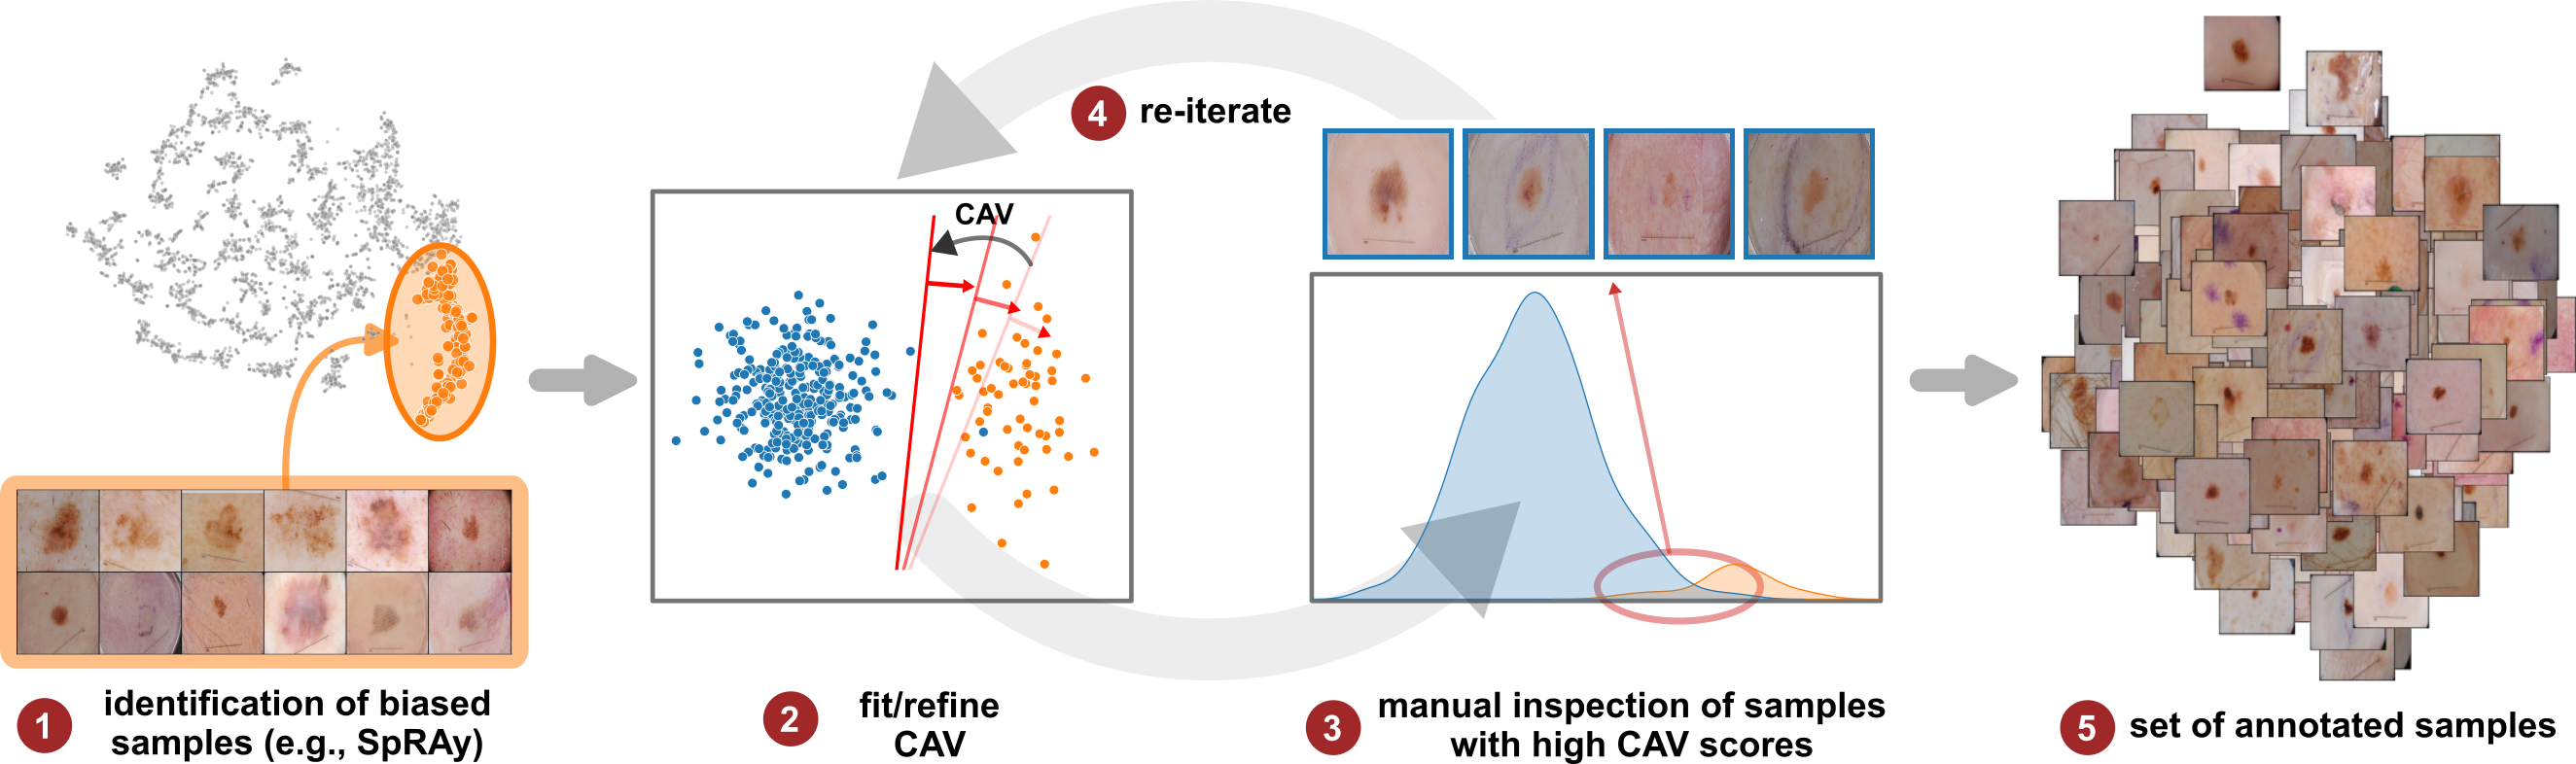

Iterative Refinement of Bias Model

Concept representations can be refined iteratively by correcting labeling errors in the data (step ( ) in Fig. 1). Specifically, non-artifactual and unknown samples with high bias scores are subject to manual inspection to improve the label quality and concept representation, as shown in Fig. 3. Starting with ( ) a small set of bias samples obtained from bias identification methods, ( ) an initial CAV is fitted. Next, ( ) manual inspection of samples with high bias scores improves the label quality. The updated labels are used to ( ) iteratively refine the CAV, ( ) resulting in a set of annotated bias samples.

Both input and latent relevance clustering require subsequent human supervision to determine whether outlier clusters represent valid or spurious behavior. To semi-automate this process, Anders et al. [3] propose using Fisher Discriminant Analysis [37] to rank class-wise clusterings by linear separability, while Dreyer et al. [27] computes similarities between prototypes. The results of clustering approaches can serve as an initial set for bias modeling methods outlined in Sec. 3.2, which can be refined iteratively. An example outlier cluster of latent relevances is shown in Fig. 4 (top), with all samples containing the spurious band-aid concept.